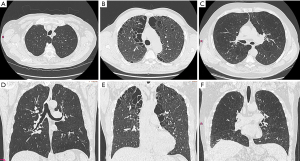

CT

Due to its high spatial resolution, the opportunity of three-dimensional reformation and quantification CT is the preferred imaging modality in the evaluation of lung emphysema. CT allows for an easy quantification and characterization of emphysematous destructed lung (19,20). CT is also the imaging modality of choice when it is up to assess heterogeneity and distribution of emphysematous lung changes when it is up to find suitable candidates for LVR or endobronchial valve placement: The National Emphysema Treatment Trial (NETT) for example, revealed that subjects with upper lobe predominant or heterogeneous emphysematous changes are benefitting the most from LVR (5), while patients with a homogeneous distribution had a lesser beneficial effect after treatment.

CT is also used to identify concomitant conditions such as malignancy and airway involvement (i.e., bronchiectasis, tracheomalacia, lung compression, mucus plugging and thickening of the bronchial walls) (19). Moreover, with CT it is possible to detect the presence of air trapping and bronchial wall collapse, when additional expiratory CT series are acquired (4).

Semiquantitative evaluation uses simple methods which do not require the use of sophisticated software: for instance, by (I) sagittal reformations, and (II) colour coding the severity and distribution of emphysema using the CT densitometry can be performed. Further, CT densitometry images enable for a precise, less observer-dependent evaluation of emphysematous lung changes compared to axial and multiplanar CT images and have therefore potential to be used in LVR surgery planning (23).

To date, quantitative methods are the gold standard in the assessment of and manifold commercially available software tools allow for an automated quantification of lung emphysema. The first step is to virtually remove other anatomic structures such as the chest wall and the mediastinum from the lung parenchyma. In a second step, the remaining lung parenchyma is evaluated voxel by voxel for different CT attenuations, the so-called Hounsfield Units (HU). HU are used to measure the density of each voxel and according to generally accepted thresholds [Gevenois et al. (24,25) recommended a cut-off value for lung emphysema on CT scans is –950 HU] it is possible to distinguish normal lung tissue from emphysema (19,26). Finally, the burden of emphysema is defined as the relative amount of lung parenchyma inferior to the chosen threshold. Both, the observer and the software based method, can be used additionally for the classification of the anatomic distribution of emphysematous lung changes (6). Newer and more sophisticated techniques allow for a depiction of emphysema clusters, providing more profound information on heterogeneity (27). Despite the above mentioned semi-quantitative and quantitative approaches, the validation of the source images remains crucial in order to don’t overlook concomitant findings such as malignancies, infections or evaluation of fissures.